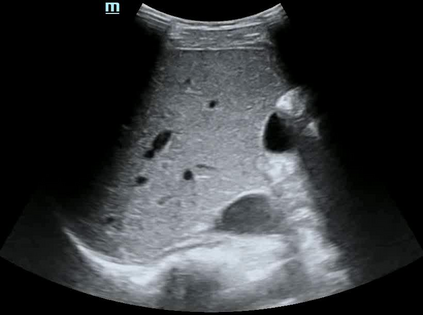

Most deep neural networks (DNNs) based ultrasound (US) medical image analysis models use pretrained backbones (e.g., ImageNet) for better model generalization. However, the domain gap between natural and medical images causes an inevitable performance bottleneck. To alleviate this problem, an US dataset named US-4 is constructed for direct pretraining on the same domain. It contains over 23,000 images from four US video sub-datasets. To learn robust features from US-4, we propose an US semi-supervised contrastive learning method, named USCL, for pretraining. In order to avoid high similarities between negative pairs as well as mine abundant visual features from limited US videos, USCL adopts a sample pair generation method to enrich the feature involved in a single step of contrastive optimization. Extensive experiments on several downstream tasks show the superiority of USCL pretraining against ImageNet pretraining and other state-of-the-art (SOTA) pretraining approaches. In particular, USCL pretrained backbone achieves fine-tuning accuracy of over 94% on POCUS dataset, which is 10% higher than 84% of the ImageNet pretrained model. The source codes of this work are available at https://github.com/983632847/USCL.